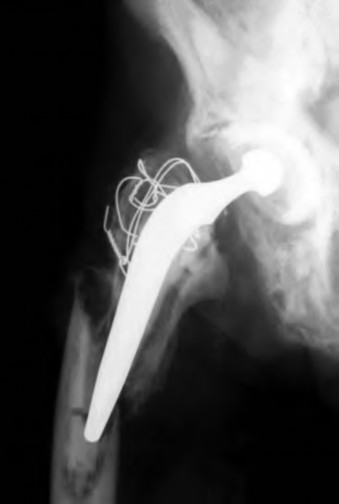

A 72-year-old female falls and sustains a periprosthetic femur fracture around her cementless total hip arthroplasty. Radiographs reveal a fracture extending just distal to the tip of the stem. The stem is radiographically loose, but there is excellent proximal and distal bone stock. According to the Vancouver classification, what is the fracture type and the recommended surgical treatment?

Explanation

Question 23

A 75-year-old female sustains a fall 5 years after a cementless THA. Radiographs show a periprosthetic femur fracture occurring around the stem tip. Intraoperative assessment reveals the stem remains firmly fixed in the metaphysis, and the proximal bone stock is adequate. According to the Vancouver classification, what is the fracture type and the standard recommended treatment?

A 78-year-old female sustains a periprosthetic femur fracture 10 years after a cemented THA. Radiographs show a fracture around the tip of the stem with a loose femoral component and poor proximal bone stock, but adequate diaphyseal bone.

What is the most appropriate surgical treatment?

Question 88

A 75-year-old female sustains a periprosthetic femur fracture around a cemented polished taper slip stem. Radiographs demonstrate a fracture around the tip of the stem. The stem is radiographically loose, but the proximal bone stock is excellent (Vancouver B2).

What is the gold standard surgical management?